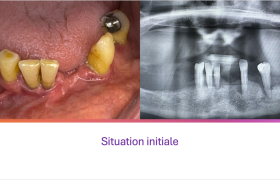

Patiente de 73 ans.

Ses dents du bas sont mobiles et douloureuses. Elles ne peuvent plus stabiliser l’ancienne prothèse du bas. La patiente vient nous voir dans l’attente d’une solution stable et esthétique.

La pose de 3 implants et les extractions sont réalisées dans la même séance; une prothèse transitoire stabilisée par 2 clips transitoires est mise en place le même jour.